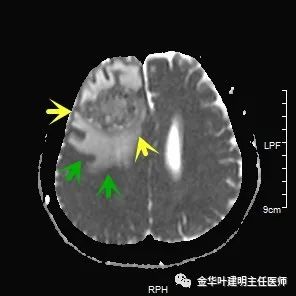

以上图示术前头颅MRI的图像,病灶明显,伴周围显著水肿,中线结构移位。基本可认为是肺癌伴脑转移。那么怎么治疗呢?需不需要手术?能不能手术?手术怎么做?先开颅还是先开肺?